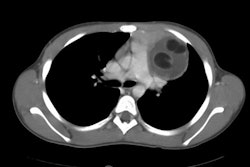

Anatomists divide the mediastinum into four parts- the superior and inferior mediastinum (separated by an imaginary line traversing the manubrial joint and the lower surface of T4), and then the inferior compartment is divided into the anterior, middle (containing the heart, major blood vessels and airways), and posterior mediastinum [2]. Felson divided the mediastinum based upon the lateral CXR with the anterior mediastinum bounded anteriorly by the sternum and posteriorly by a line drawn from the anterior aspect of the trachea and along the posterior heart border; the posterior mediastinum is defined by a line that is 1 cm posterior to the anterior edge of the vertebral bodies; and the middle mediastinal compartment lies between the anterior and posterior mediastinum [2].

Anterior medisstinal masses:

1- Prevasular masses: Lymphoma/adenoapthy, retrosternal goiter, thymic lesions, and germ cell tumors

2- Precardiac masses in contact with the diaphragm: Epicardial fat, Morgagni hernia, pleruopericardial cysts, and adenopathy